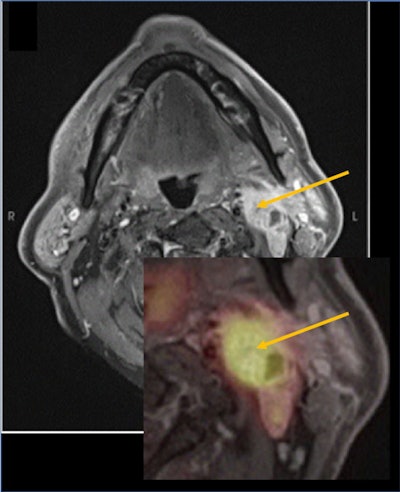

Metastatic lymph nodes in head and neck squamous cell carcinoma with contrast enhancement and high standardized uptake value (SUV). Figure courtesy of Dr. Nadya Pyatigorskaya, PhD, and presented at ISMRM 2023.

Metastatic lymph nodes in head and neck squamous cell carcinoma with contrast enhancement and high standardized uptake value (SUV). Figure courtesy of Dr. Nadya Pyatigorskaya, PhD, and presented at ISMRM 2023.Cancers of the upper aerodigestive tract mostly consist of head and neck squamous cell carcinomas (HNSCCs), which account for 90% of stage I head and neck cancers and represent the sixth most common cancer worldwide. HNSCC have a high recurrence rate and represent one of the most common histological types to metastasize to regional lymph nodes, Pyatigorskaya explained in an e-poster presentation on 7 June at the International Society for Magnetic Resonance in Medicine (ISMRM) meeting in Toronto.